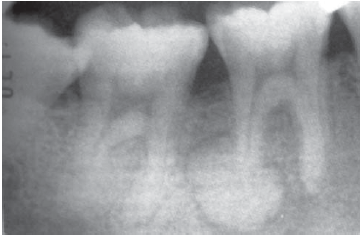

As Figuras 1 e 2 mostram radiografias periapicais do elemento 47 de um paciente que se apresentou com dor espontânea, aguda e persistente.

Lesão radiopaca associada à raiz distal do elemento 46.

Paciente do sexo masculino, 25 anos, leucoderma, foi submetido a exame radiográfico periapical completo para iniciar o tratamento ortodôntico. Durante a avaliação de tal exame, o cirurgião-dentista observou uma massa radiopaca apresentando halo radiolúcido no ápice da raiz distal do dente 46 (figura acima). O teste de vitalidade pulpar indicou que esse elemento era vital.

Diante desses achados, o diagnóstico e a conduta a serem realizados são, respectivamente,